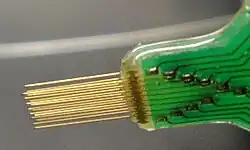

Neural Interface

Neural interface system provides a direct communication pathway between the nervous system and the outside world by stimulating or by recording from neural tissue to help people with sensory, motor, or other disabilities of neural function. These research is called a new branch of experimental neuroscience, variously named brain-machine interfaces (BMIs), brain-computer interfaces (BCIs), neural prostheses, or neural interface systems (NISs). An electronics package in each device activates an array of tiny electrodes that contact healthy neurons in the body. Signals by the electrodes bypass damaged areas of the brain or part of the nervous system to restore function, block pain, or prevent seizures. Although electrical stimulation systems have already broadly used for clinical application, neural interfaces that record and decipher neural signals are just starting for clinically systems to assist impaired people. The examples of the successful neural interfaces include the cochlear implant[28][29] to provides a sense of sound to people with severe hearing impairment and the deep brain stimulator (DBS) [30] to help prevent seizures in patients with epilepsy and Parkinson’s disease.

Since the late 1990, neural interface studies have developed remarkably on the basis of the closed-loop control using neuronal spikes. Chapin and colleagues showed a rat's ability to control a one-dimensional feeder through multielectrode recordings from sensorimotor cortex[31]. After that, a lot of studies(Carmena et al. 2003[32], Musallam et al. 2004[33], Santhanam et al. 2006[34],Taylor et al. 2002[35] and so on) demonstrated that closed-loop control in primates is available. The common closed-loop neural interface system is composed of four components: (1) a recording array that extracts neural signals, (2) a decoding algorithm that translates these neural signals into a set of command signals, (3)an output device that is controlled by these command signals, and (4) sensory feedback in the form of vision and potentially other sensory modalities.

Neural implants must be designed to be as tiny as possible so as to be minimally invasive, in special areas srrounding the brain, eyes or cochlea. These implants communicate with their prosthetic counterparts wirelessly. In addition, power is currently received through wireless power transmission through the skin. Usually, the tissue near the implant is highly sensitive to temperature rise. It means that power consumption must be minimal to avoid tissue damage.[36]

Input Electrode

Intracranial electrodes is composed of conductive electrode arrays implanted on a polymer or silicon, or a wire electrode with an exposed tip and insulation for the part that stimulation or recording is not needed.

Current implantable microelectrodes could not record single- or multi-unit activity depending on a chronic scale. Lebedev and Nicolelis reviewed the specific needs in the field to truly improve the technology to the level of clinical implementation. In short, the 4 requirements in their review are:

- Consistent long term (over the years) recording of large neuronal populations in multiple brain areas;

- Efficient processing of recorded data;

- Incorporation of feedback into the user’s body using native plasticity;

- Advances in prosthetic technology to create artificial limbs which can reproduce the full motion.[37][38]

Hardware

Chips have incorporated a various amount of data compression on chip[39], containing spike sorting (Chae et al., 2009). While a lot of systems have too high power consumption in order to be powered from a battery implant, Sarpeshkar et al have fabricated amplifiers and analog to digital converters at a power costless than 9 uW per 20 ksps channel[40]. Although the small area and low power consumption of available integrated circuits is enough to process most of channels of neural data, some problem should be resolved. For instance, how long the implant can stay in the body? Electronics coated with 6 um parylene C have been proved to work for up to 276 days[41]. Commercial systems such as Plexon, Tucker Davis, NeuroLynx, and so on depend on hermetically sealed feed-through connectors into a welded titanium casing, in which the electronics are housed. But, Brain machine interfaces which use hundreds of electrodes and high-density miniature hermetic feedthroughs do not exist yet.